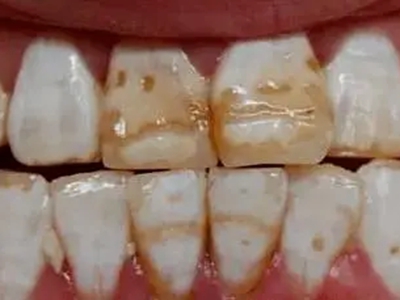

牙釉质发育不全牙齿棕色有缺损图

牙釉质发育不全患者牙齿出现明显的缺损表现,并于表面形成深褐色的蜂窝状、竖条状的凹坑,甚至形成洞,患者上下牙失去咬合能力。

牙釉质发育不全牙齿表面棕色有坑图

牙釉质发育不全导致牙釉质表面呈棕褐色,有带状、窝沟状凹陷,以及黑点,牙釉质大面积缺损,牙齿表面变得粗糙,可出现进食时敏感等不适。